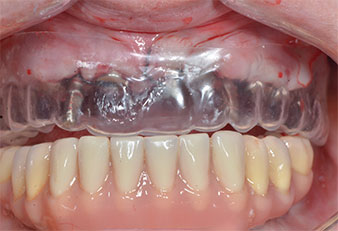

Plastic template

Fig. 9: A plastic template reveals sufficient space for the existing prosthesis to serve as a temporary retained on the provisional implants.